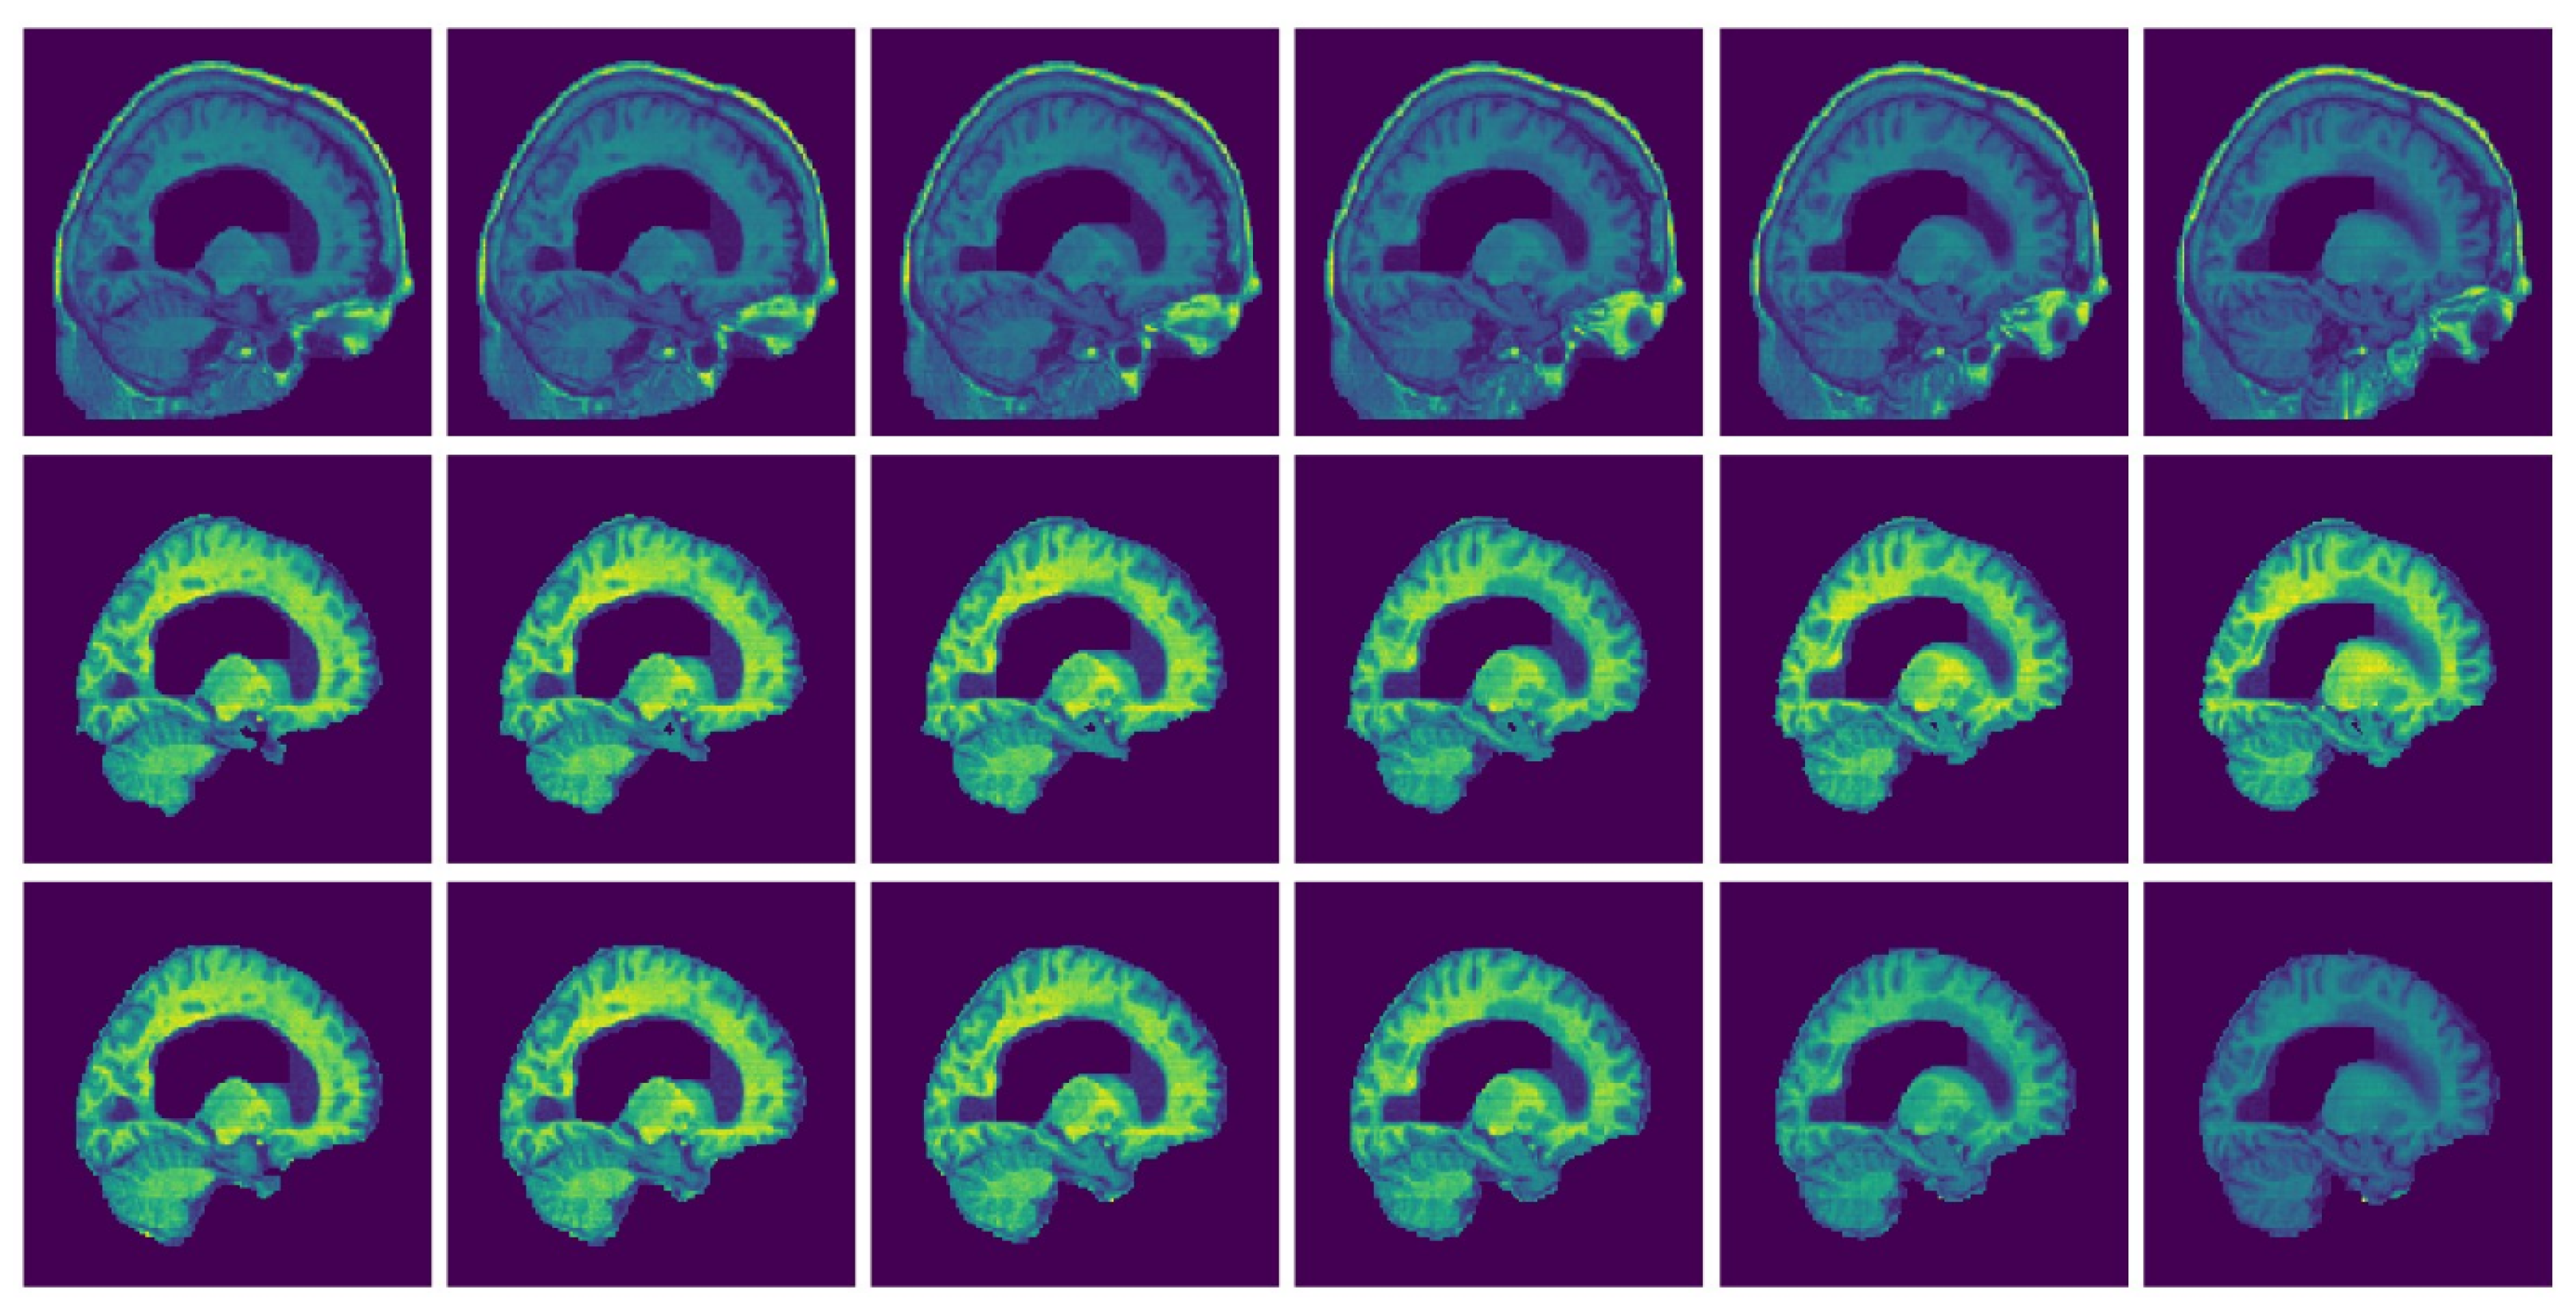

Figure 9 and Figure 10 present examples of a visual comparison of 2D slices segmented from two different subjects from IBSR and OASIS data sets, respectively. Notice that for Figure 9, the original sagittal sections show that some parts of the 3D head were cut. Figure 10 also present representative sagittal sections from a single subject. Since the proposed approach depends on sampling points within different regions, tuning the parameters for extracting the brain from the two compared MRI volumes (Figure 9 and Figure 10) can differ significantly.

Selected MRI slices (IBSR data set): Sagittal MRI plane segmented brain. Row one: Input images, Row two: Predicted brain and Row three: Ground truth brain.

Selected MRI slices (OASIS data set): Sagittal MRI plane segmented brain. Row one: Input images, Row two: Predicted brain and Row three: Ground truth brain.